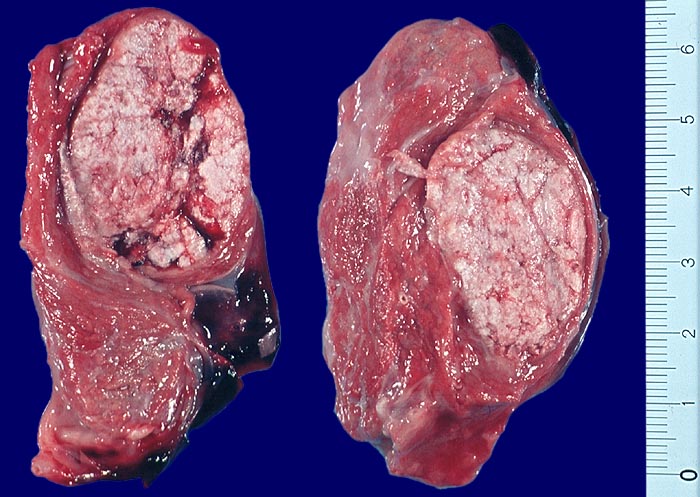

- Anschnitt eines grossen mikrofollikulären Knotens (autonomes Adenom) mit angedeuteter Kapsel und zentraler Einblutung. Oben zwei weitere kleine Satellitenknoten.